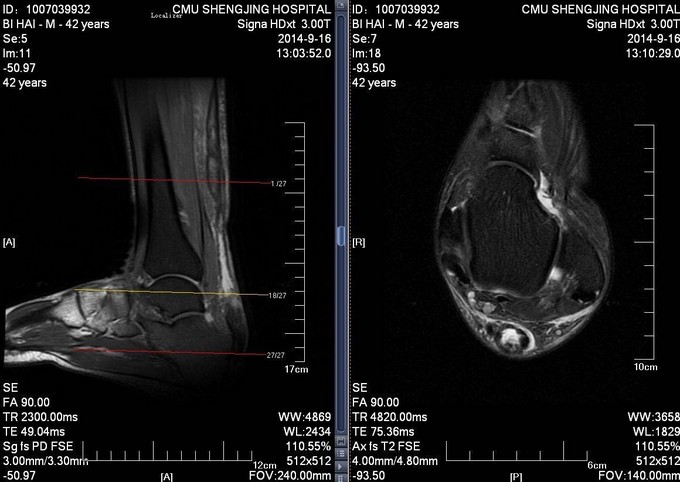

患者于2014年7月28日打排球时不慎摔伤,自觉左足跟部一过性剧烈疼痛,意识清醒。自觉足跟部及小腿后侧远端疼痛、行走时左足无力。于2014年9月10日就诊于当地医院,行相关查体后提示:左脚跟腱断裂。患者为进一步治疗门诊以“左跟腱断裂”为诊断收入病房

患者生命体征平稳,跟腱后方凹陷。局部可触及缺损,Thompson征阳性。

诊断:左陈旧性跟腱断裂 入院完善检查后,行左跟腱翻转修补术,术后踝关节跖屈石膏固定。